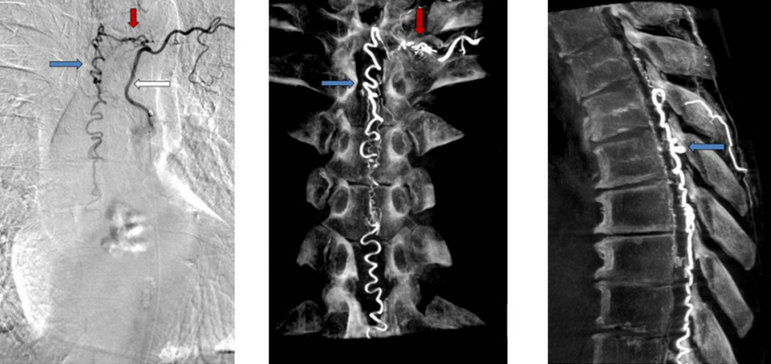

Spinal vascular malformations are a group of blood vessel disorders any of which can lead to spinal cord dysfunction or damage. There are 4 subtypes of spinal vascular malformations and each one has unique causes and and different treatments. Read more…